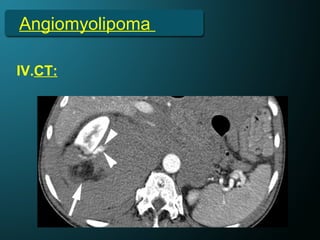

IV.CT:

NECT:

• Well circumscribed round or

oval cortical masses.

• Fat.

Angiomyolipoma

CECT:

• Early/CTA → +/- Aneurysm.

• Nephrographic Phase → +/-Heterogeneous

enhancement.